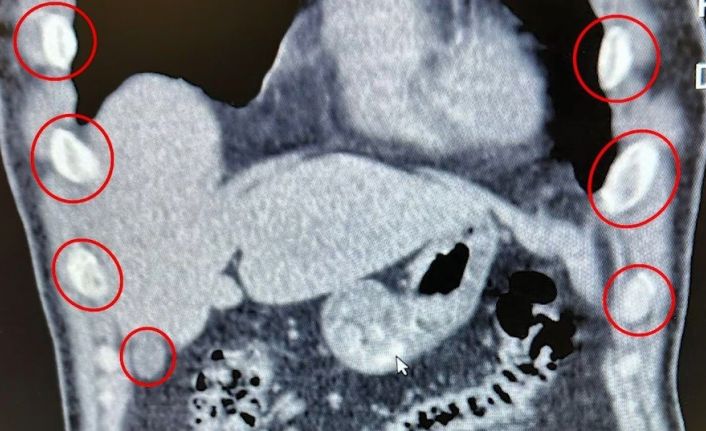

Bitlis İl Emniyet Müdürlüğü Narkotik Suçlarla Mücadele Şube Müdürlüğü ekipleri, uyuşturucu ile mücadele kapsamında önemli bir operasyona imza attı. Tatvan ilçesinde durdurulan bir otobüste yolcu olarak seyahat eden yabancı uyruklu 2 kişi gözaltına alındı. Şahısların yapılan tıbbi müdahalesinde, yuttukları 136 kapsül halinde toplam 1 kilo 48 gram metamfetamin ele geçirildi.